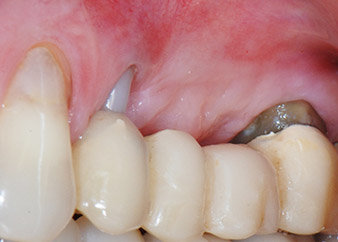

След един месец, в деня на операцията, болката и възпалението в зъб 24 е минимално, но подвижността в Miller class 2 е на лице. След отваряне на ламбата и почистването на периапикалната и перирадикуларната тъкани, обхватът на костния дефект стана очевиден (Фиг. 2 и 3).

В букалния корен, цялата вестибуларна и дистална кост липсва. Захващането е значително ограничено до палатиналния корен, подчертавайки предварително лошата прогноза. Зъб 27 също откри намалено хоризонтално захващане и минимално апикално разреждане (Фиг. 1) без клинични симптоми.